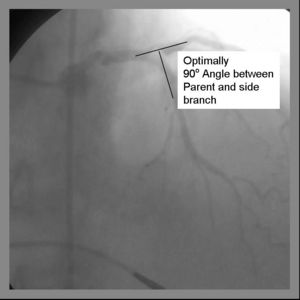

May use a 6Fr Guiding system Final Kissing balloon inflation required due to high Restenosis rate Ideal angle of bifurcation is at or near 90 degrees.